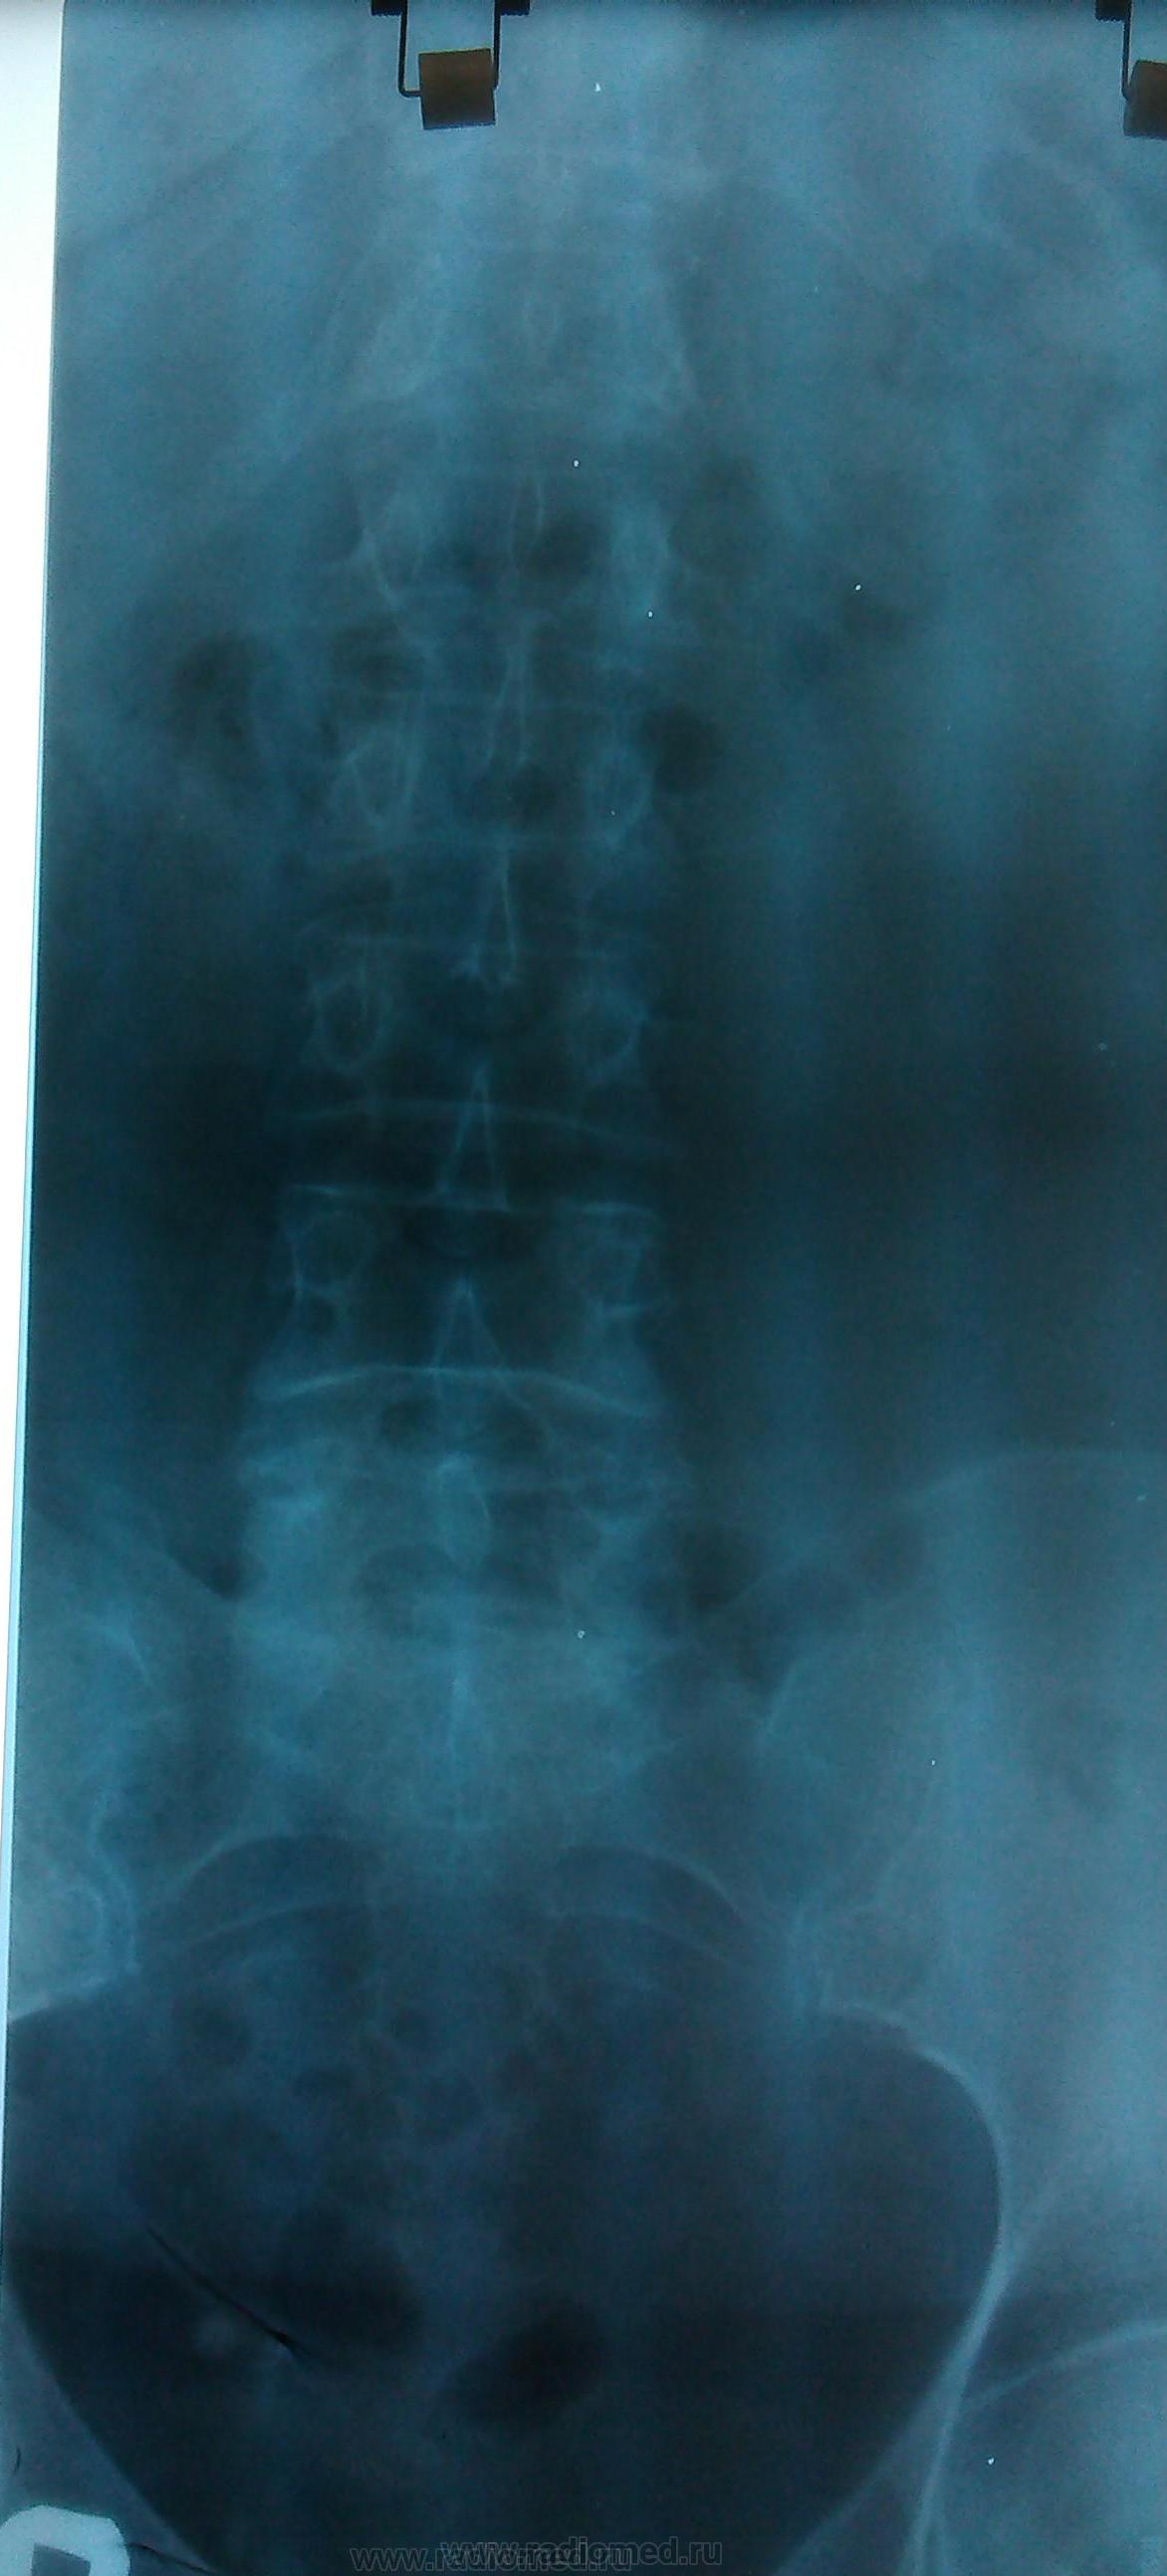

Пол пациента: Женский пол Тип патологии: Другое Область исследования: Скелетно-мышечная система Методы исследования: Rg Пациентка, 62 г. Направительный диагноз: Остеохондроз ПОП? Непонятен L2. https://radiomed.ru/sites/default/files/styles/case_slider_image/public/user/18609/img_20131213_130008.jpg?itok=21kdbd6P https://radiomed.ru/sites/default/files/styles/case_slider_image/public/user/2841/img_201090.jpg?itok=1DUnF6FR https://radiomed.ru/sites/default/files/styles/case_slider_image/public/user/2841/img_20131213shch86.jpg?itok=uhYLrNy7 ID:34193 Вс, 15/12/2013 - 17:30 #1 Mila85 Не на сайте Был на сайте: 3 года 5 месяцев назад Зарегистрирован: 15.03.2012 - 16:59 Публикации: 1790 Обычный L2 вроде, в таком возрасте уже системный остеопороз вероятен с изменением формы позвонков Вс, 15/12/2013 - 18:30 #2 И.Бондаренко Не на сайте Был на сайте: 2 часа 48 минут назад Зарегистрирован: 13.09.2011 - 22:55 Публикации: 9211 Качество фото ужасное. Что можно сказать? Вс, 15/12/2013 - 19:35 #3 алкс Не на сайте Был на сайте: 10 лет 4 месяцев назад Зарегистрирован: 24.10.2012 - 22:55 Публикации: 2915 И.Бондаренко wrote: Качество фото ужасное. Что можно сказать? ! Можно сказать, что явных деструкций не видно. Вс, 15/12/2013 - 20:41 #4 Катенёв Валенти... Не на сайте Был на сайте: 7 лет 4 месяцев назад Зарегистрирован: 22.03.2008 - 22:15 Публикации: 54876 Да, выставляемые иллюстрации желают быть много лучше. Вс, 15/12/2013 - 20:50 #5 Евгений Дорофеев Не на сайте Был на сайте: 11 лет 5 месяцев назад Зарегистрирован: 06.06.2013 - 17:28 Публикации: 1746 Постарался обработать, но качество снимков самих не ice(по моему перебиты).Приложения:

Обычный L2 вроде, в таком возрасте уже системный остеопороз вероятен с изменением формы позвонков

Постарался обработать, но качество снимков самих не ice(по моему перебиты).